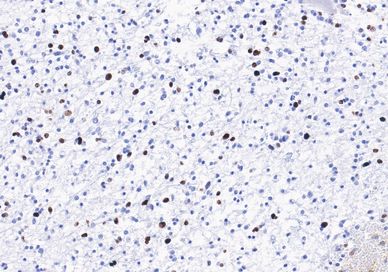

Immunohistochemical staining reveals loss of H3K27Me3 expression by neoplastic cells.

In view of these results, the tumor was reclassified as a pediatric-type high-grade glioma (courtesy of Dr. Daniel Marker, UPMC Neuropathology Center of Excellence) and the specimen was submitted for additional methylomic studies.

Methylation profile indicated a match to diffuse midline glioma H3 K27M mutant with a high confidence score, and the tumor was classified as a diffuse midline glioma, H3 K27-altered, CNS WHO grade 4.